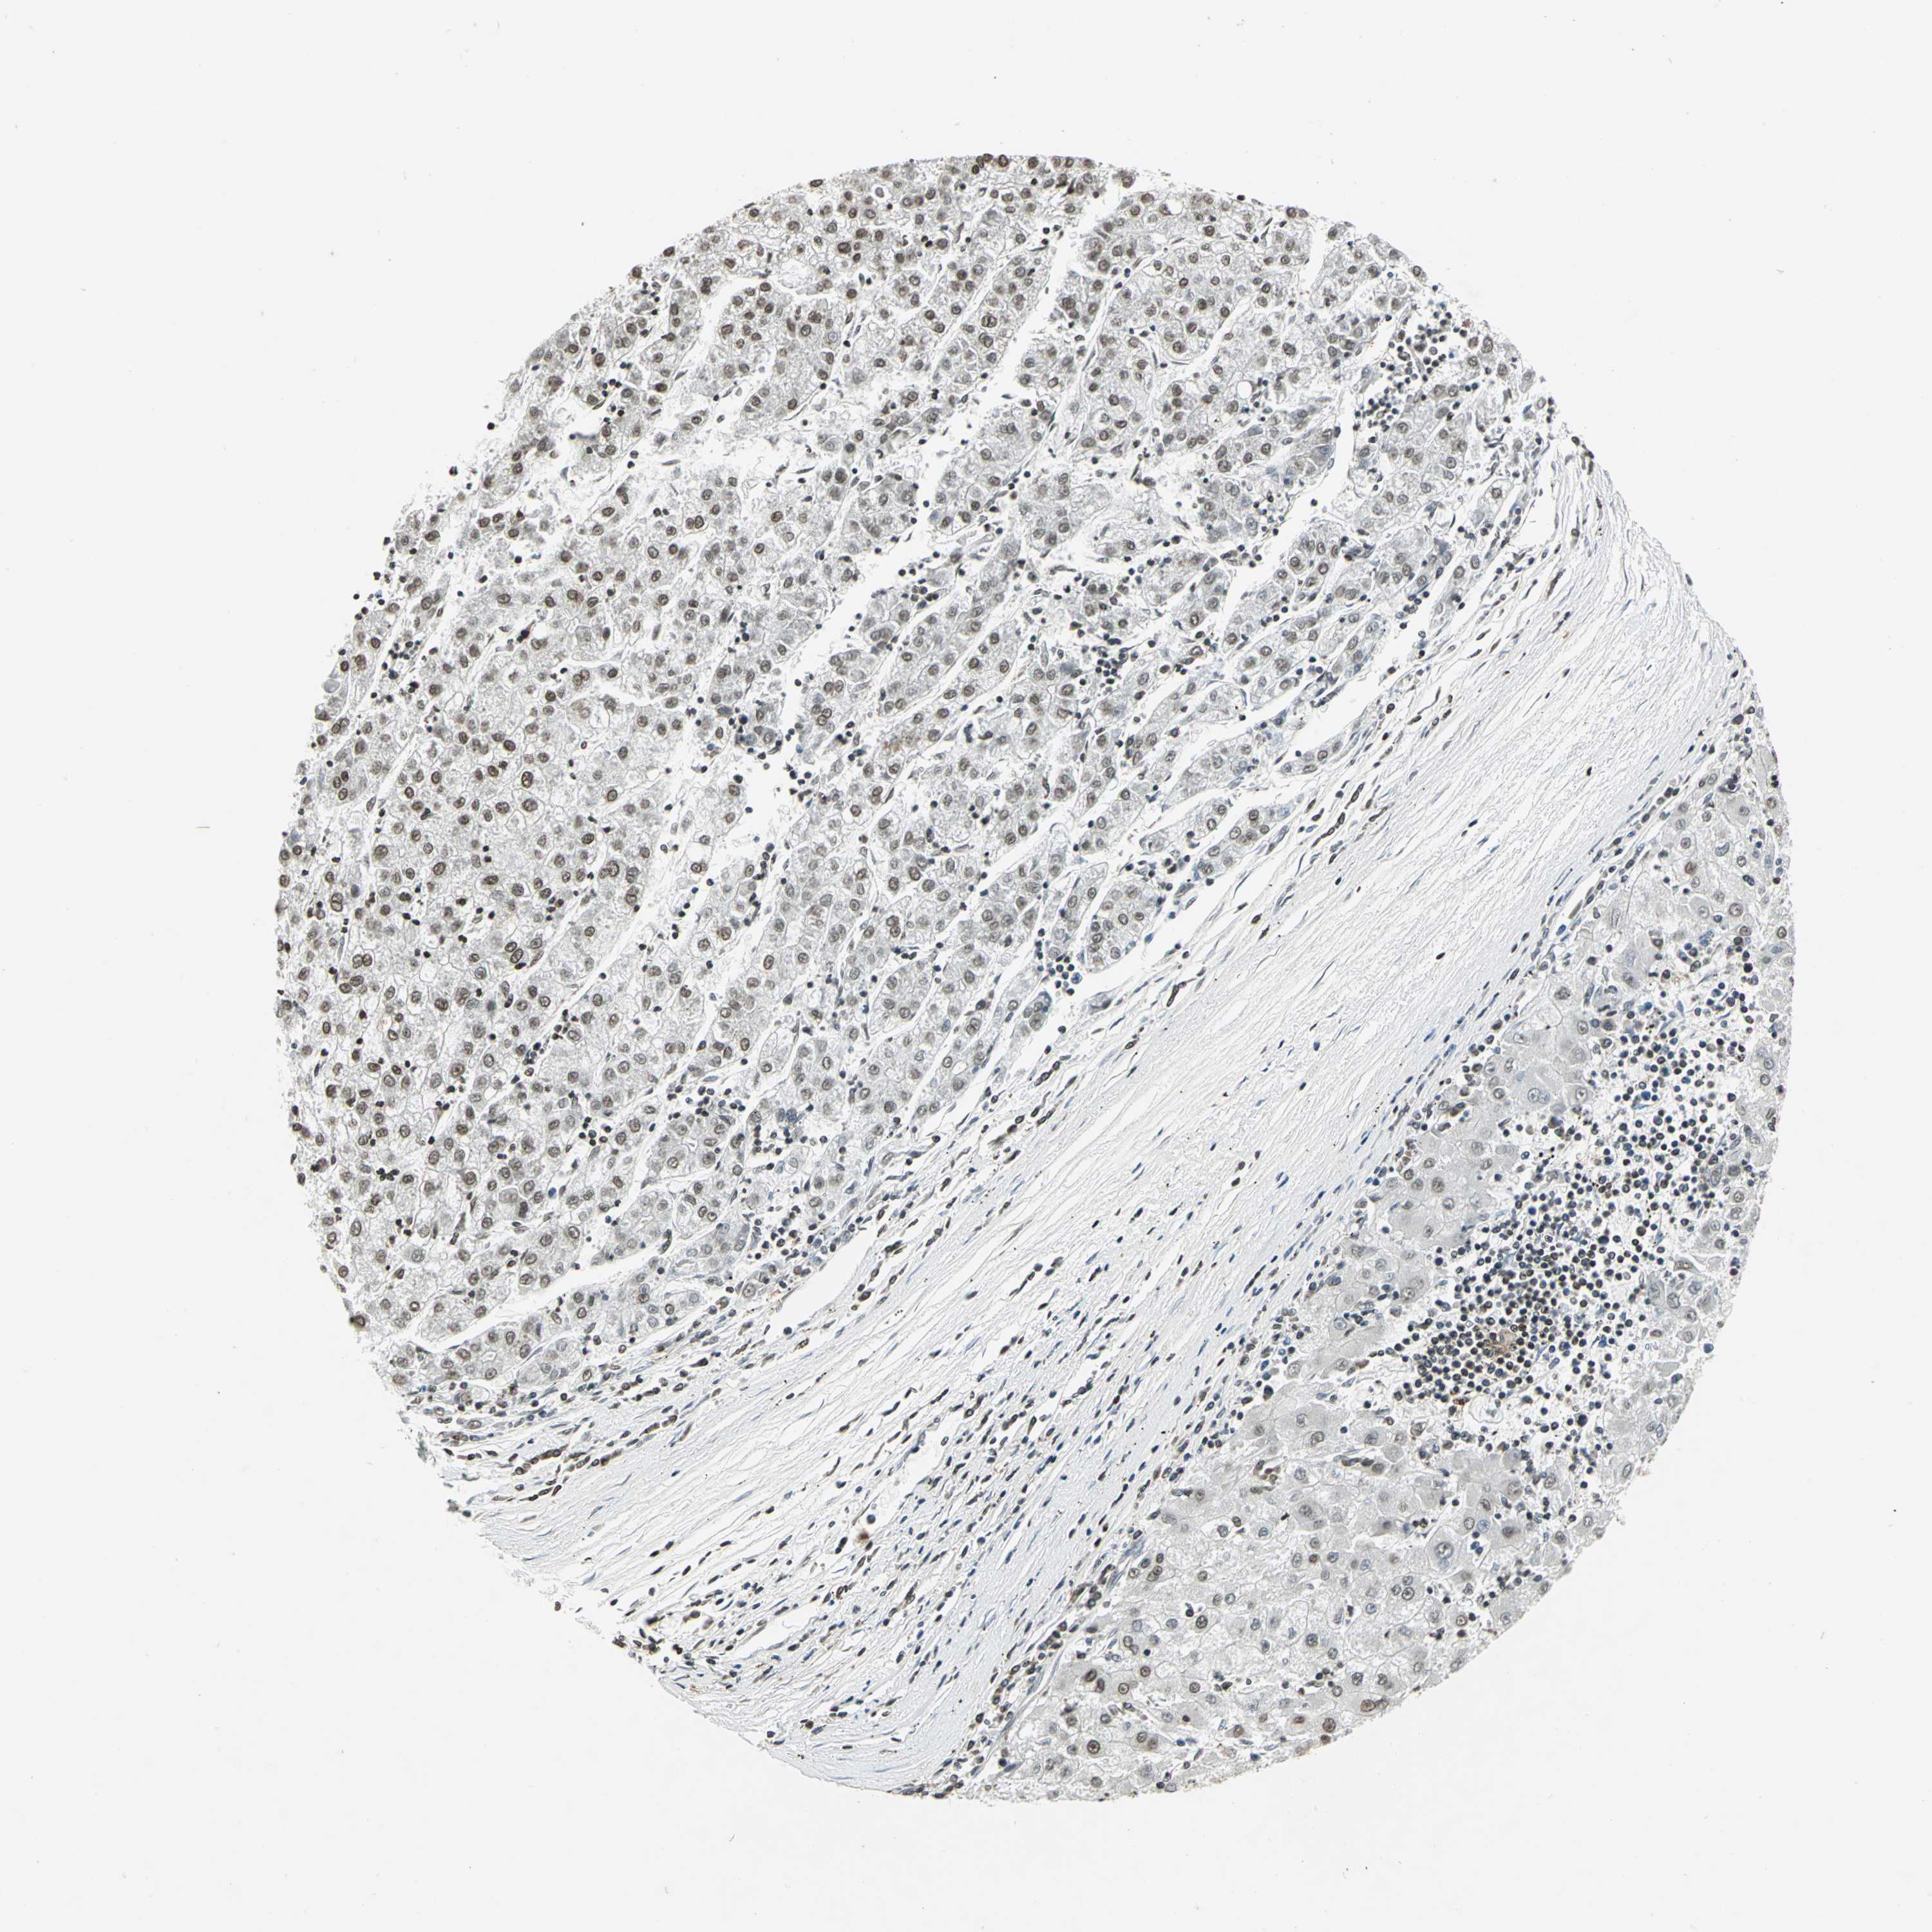

LIVER CANCER - Protein expressioni

A mouse-over function shows sample information and annotation data. Click on an image to view it in a full screen mode. Samples can be filtered based on level of antibody staining by selecting one or several of the following categories: high, medium, low and not detected. The assay and annotation is described here.

Antibody stainingi

Antibody staining in the annotated cell types in the current human tissue is reported as not detected, low, medium, or high, based on conventional immunohistochemistry profiling in selected tissues. This score is based on the combination of the staining intensity and fraction of stained cells.

Each image is clickable and will lead to virtual microscopy that enables deeper exploration of all samples and also displays staining intensity scores, fraction scores and subcellular localization as well as patient and tissue information for each sample.

Antibody HPA003162

Antibody CAB005191

Staining

High

Medium

Low

Not detected

Intensity

Strong

Moderate

Weak

Negative

Quantity

>75%

75%-25%

<25%

None

Location

Nuclear

Cytoplasmic/membranous

Cytoplasmic/membranous,nuclear

Carcinoma, Hepatocellular, NOS

Cholangiocarcinoma